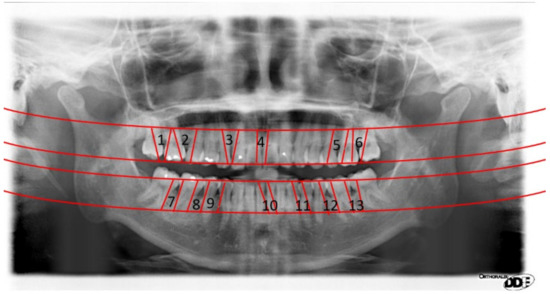

2.2.3. Positioning Numbers

3. Results